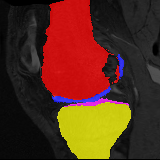

Moving

Target

Mono-0

Mono-5

DA-1

DA-5

Mono-200

Results: All trained networks are evaluated using Dice overlap scores between predictions and the manual segmentations for the segmentation network, or between the warped moving segmentations and the target segmentations for the registration network. Tabs. 1 and 2 show results for the knee and brain MRI experiments respectively in Dice scores (%). Fig. 2 shows examples of knee MRI registrations and brain MRI segmentations.

Qualitative results: DA achieves more anatomically consistent registrations than the mono-networks on the knee (Fig. 2) and Brain MRI samples (see supplementary material).